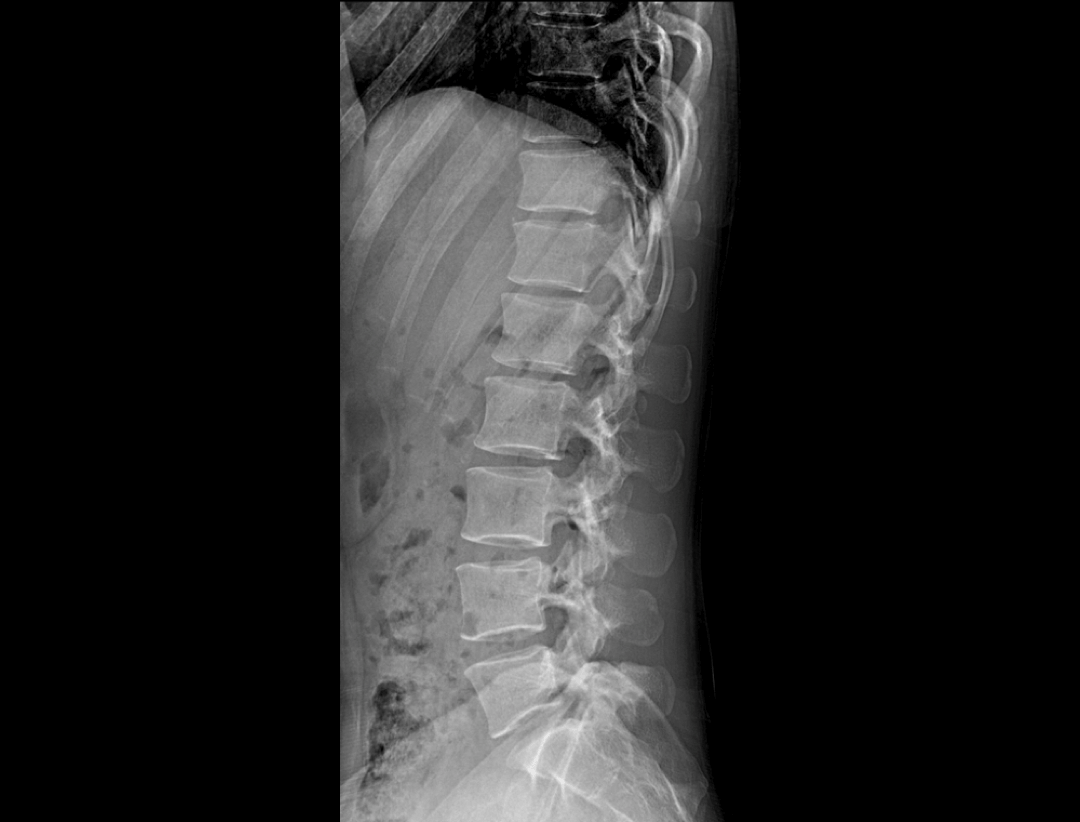

集成脊柱Cobb角及股骨颈干角测量功能,精准指导外科手术及术后评估。